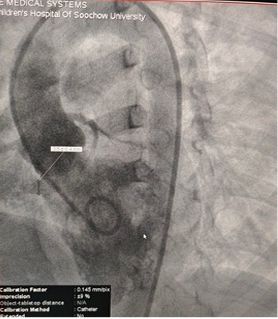

Case Sharing | Successful Closure of Multi-Exit Membranous Septal Aneurysm-Type VSD Using MemoSorb Biodegradable Occluder

Resultados pré-operatórios do eco:

Diâmetro base: ~ 6.1mm com saída múltipla pontos

Tecido semelhante a membrana observado sobre o defeito

Doppler colorido: fluxo de derivação da esquerda para a direita

Diagnóstico: VSD perimembranoso

Desafio: Múltiplas saídas frágeis membrana tecido

Selected MemoSorb ABFDQ-II 9 occluder based on intraoperative angiography and echocardiographic assessment.